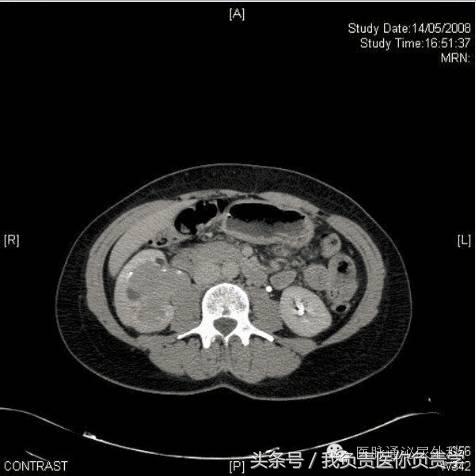

CT尿路造影的轴向图像以及相关的矢状重建,显示右肾盂中存在大面积充盈缺损。充盈缺损延伸并占据右肾盂中多数空间,造成肾造影显影期质量效应和肾脏增强的相对延迟(图2,3)。放射学表现和无痛性血尿及尿液细胞学阳性共同指示上尿路上皮癌。

图2

图3

在该病例中,经患者同意进行了膀胱镜检查,结果显示膀胱正常,未见任何外生肿瘤。CT尿路造影时发现右肾盂中的大面积充盈缺损结合尿细胞学检查阳性,将该患者确诊为上尿路上皮癌。